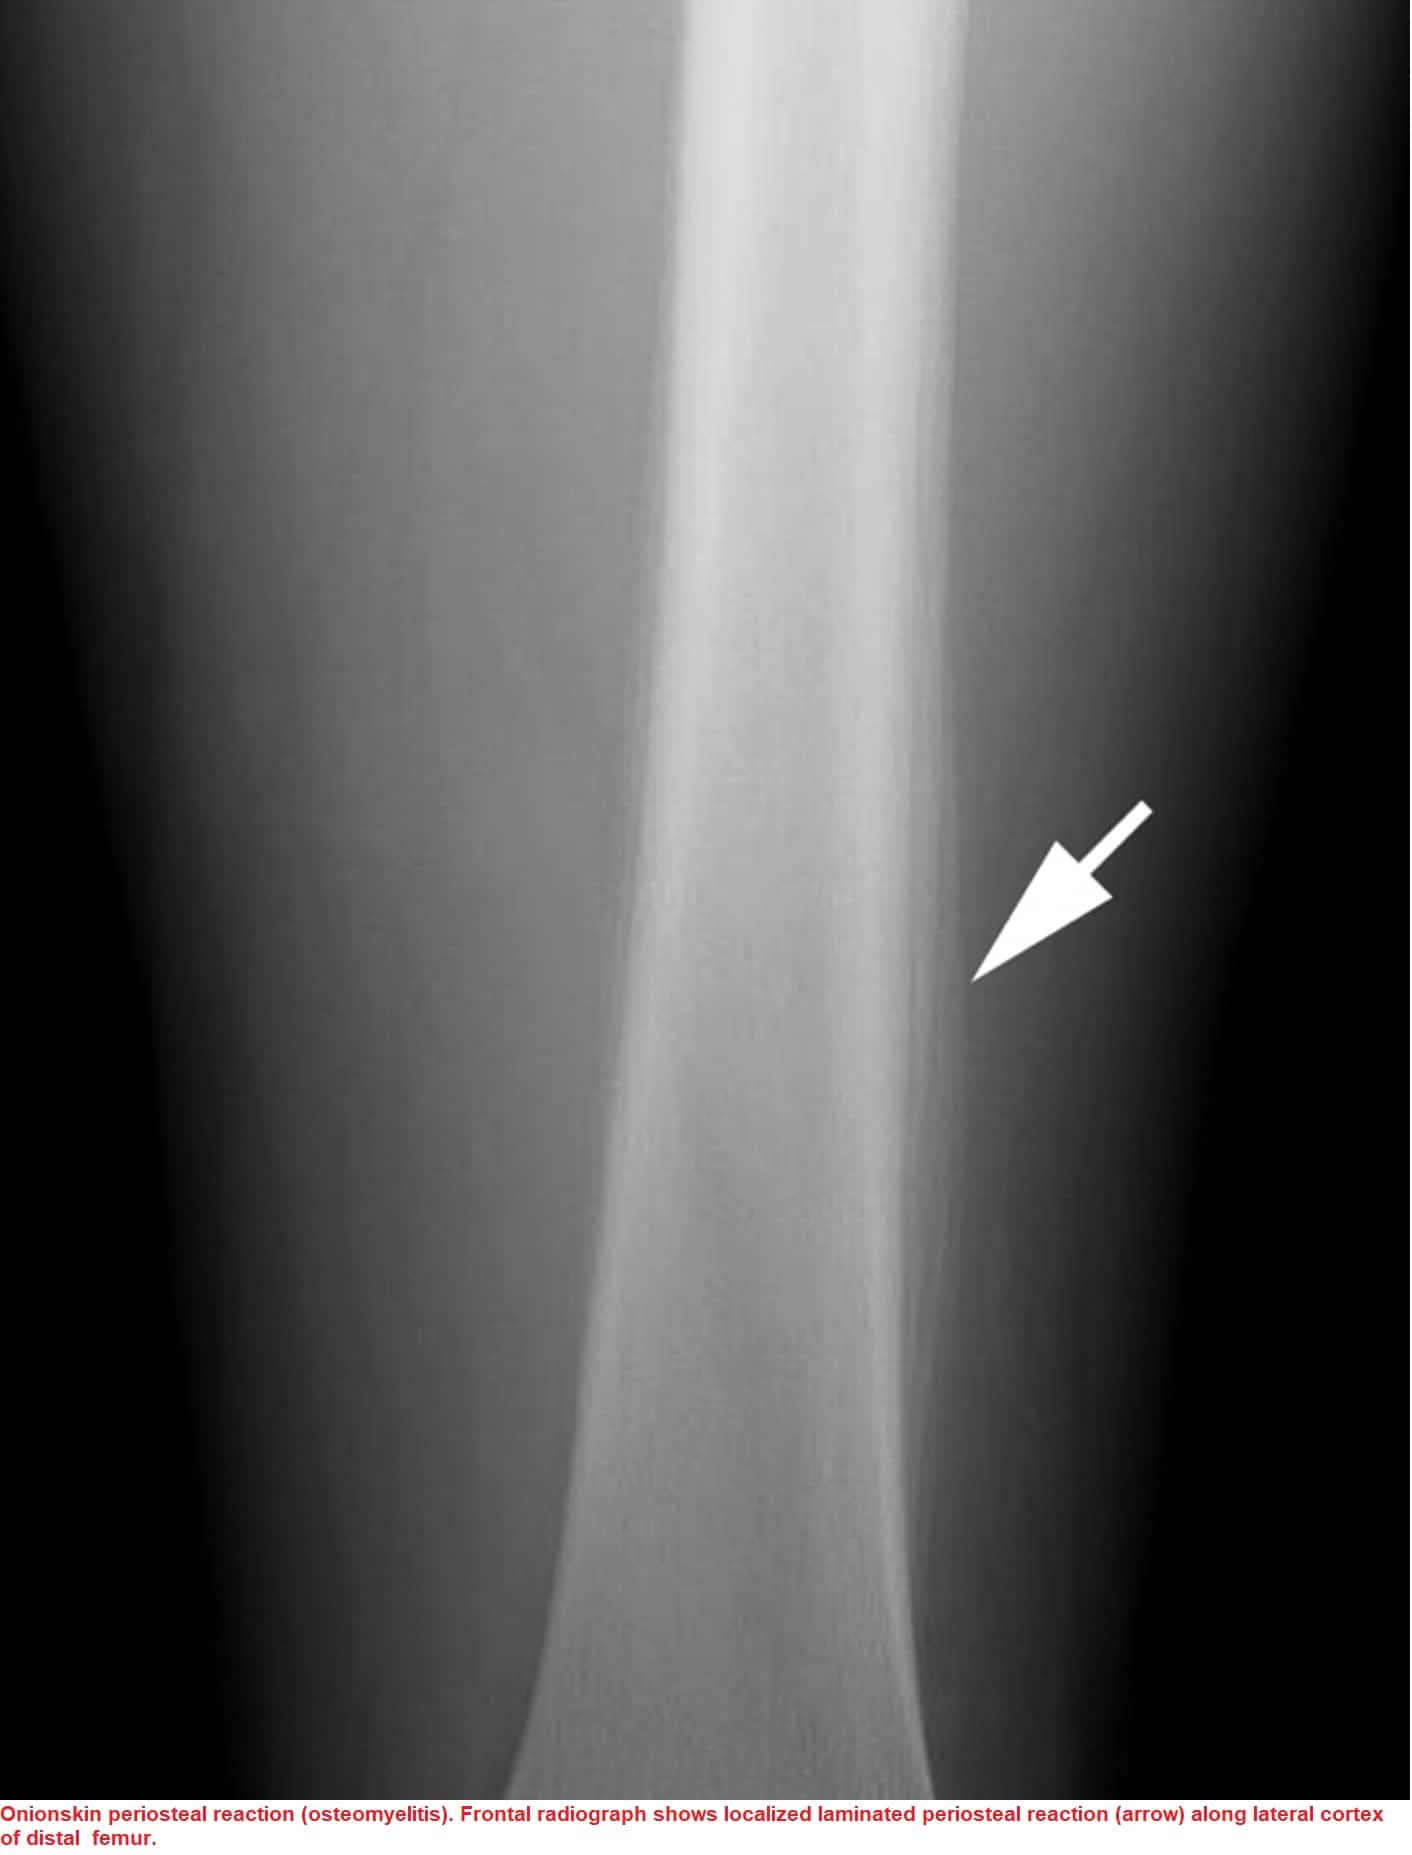

Onion Skin Appearance Osteomyelitis . Multilayered periosteal reaction, also known as a lamellated or onion skin periosteal reaction, demonstrates multiple concentric parallel layers of new bone adjacent to the. Radiographically po is characterized by the. The most common cause for po is periapical infection of mandibular first molar. The most common cause for po is periapical infection of mandibular first molar. 3 the ct imaging features of periostitis ossificans include cortical thinning and periosteal thickening with lamellar appearance. Multilayered periosteal reaction, also known as lamellated or onion skin periosteal reaction, shows multiple concentric layers of new bone adjacent to the cortex. Intraoral periapical radiograph is helpful in cases of deep carious lesions in. Osteosarcoma of the distal femur, demonstating dense tumor. In young adults, there may sometimes be subperiosteal new bone formation that appears as a thin radiopaque line along the lower border of the mandible, which gives onion. Po is a nonsuppurative type of osteomyelitis.

Po is a nonsuppurative type of osteomyelitis. In young adults, there may sometimes be subperiosteal new bone formation that appears as a thin radiopaque line along the lower border of the mandible, which gives onion. Multilayered periosteal reaction, also known as a lamellated or onion skin periosteal reaction, demonstrates multiple concentric parallel layers of new bone adjacent to the. The most common cause for po is periapical infection of mandibular first molar. Osteosarcoma of the distal femur, demonstating dense tumor. Multilayered periosteal reaction, also known as lamellated or onion skin periosteal reaction, shows multiple concentric layers of new bone adjacent to the cortex. Radiographically po is characterized by the. Intraoral periapical radiograph is helpful in cases of deep carious lesions in. 3 the ct imaging features of periostitis ossificans include cortical thinning and periosteal thickening with lamellar appearance. The most common cause for po is periapical infection of mandibular first molar.